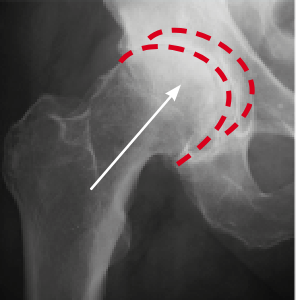

Na zdjęciu po lewo (wykonanym przed kuracją) widać niedobór mazi stawowej, który powoduje ścieranie się kości. Na zdjęciu po prawej stronie dzięki kuracji kości poruszają się płynnie i bezboleśnie. Struktura mazi stawowej się odbudowała – odzyskała właściwości poślizgowe.

Prof. Zygler udowodnił (o czym świadczą zdjęcia rentgenowskie i USG), że jego formuła antyartretyczna wpływa na regenerację stawu na trzech głównych płaszczyznach:

usuwa obrzęki stawów – dzięki likwidacji stanów zapalnych,

zmniejsza tarcie w stawach – dzięki zwiększonej produkcji doskonałej jakości cieczy synowialnej,

permanentnie eliminuje ból – dzięki regeneracji chrząstki stawowej.

Już po 4–5 tygodniach kuracji Zyglera chrząstka stawowa zmieni się z cienkiej i popękanej w grubą i sprężystą. Dzięki temu zmniejszy się tarcie w stawach, a każdy ruch będziesz wykonywać pewnie i lekko.